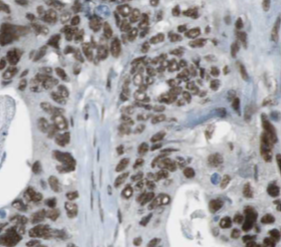

Immunohistochemistry: O-GlcNAcase/OGA/MGEA5 Antibody (9B9) [NBP3-42998] -

Immunohistochemistry: O-GlcNAcase/OGA/MGEA5 Antibody (9B9) [NBP3-42998] - Immunohistochemistry of paraffin-embedded human gliomas using (O-GlcNAcase/OGA/MGEA5 antibody) at dilution of 1:50